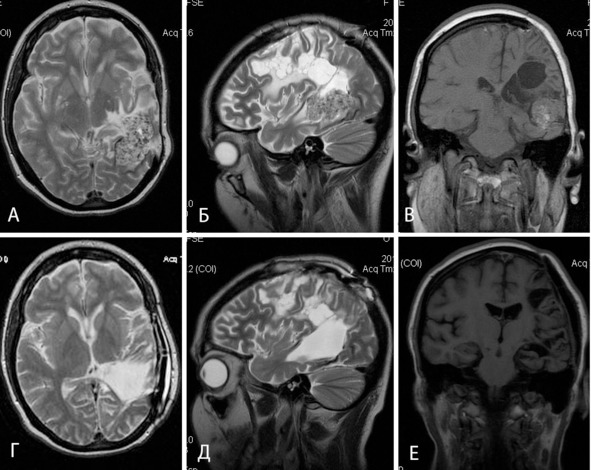

Из анамнеза известно, что пациентка госпитализирована и обследована по месту жительства в 2003 году в связи с эпизодом потери речи. При КТ выявлена гематома в левой височной доле. Выполнено удаление гематомы: во время операции осуществлен доступ к гематоме через латеральную щель, при доступе повреждена и коагулирована неуточненная ветвь СМА. Выполнена широкая декомпрессивная трепанация. За время госпитализации перенесла менинго-вентрикулит. При контрольных КТ и МРТ выявлены данные за объемное образование в задних отделах левой височной доли, кистозно-дегенеративные (постишемические) изменения в левой лобно-теменно-височной области (рисунок 6: А, Б, В). В последующем беспокоили нарушения речи, слабость в правых конечностях, тремор в левых конечностях, головные боли. Беспокоили также учащающиеся полиморфные эпилептические припадки: фокальные в правых конечностях и генерализованные судорожные (3:1).

Частота припадков постепенно нарастала и к моменту поступления в институт приступы происходили несколько раз в месяц. В неврологическом статусе выявлены выраженная сенсорная афазия, умеренный правосторонний гемипарез и правосторонняя гемигипестезия, левосторонний рубральный тремор. В ЭЭГ типичных форм эпилептической активности не выявлено. Выполнена АГ, не выявившая патологической сосудистой сети. 28.07.2009 выполнено удаление каверномы задних отделов левой височной доли и краниопластика. Во время операции выявлен и путем фрагментации тотально удален узел каверномы, осложнений не отмечено. Паталогоанатомический диагноз: кавернозная мальформация. После операции нарастания неврологического дефицита не отмечено. Со слов больной, значительно снизилась выраженность головных болей и тремора в левых конечностях. Рекомендован постоянный прием антиконвульсантов.

Больная дважды (в 2010 и 2011 гг.) являлась для контрольного осмотра. За отмеченный период зафиксирован однократный генерализованный судорожный припадок, прием антиконвульсанта продолжен в прежней дозе. Основной жалобой являются частые головные боли. В неврологическом статусе отмечается некоторое нарастание выраженности тремора в левых конечностях, однако его характер компенсирован и больная способна самостоятельно ходить. При повторных ЭЭГ данных за эпилептическую активность не выявлено. По данным контрольной МРТ кавернома удалена полностью (рисунок 6: Г, Д, Е).

Рисунок 6. Больная Р, 28 лет. До– (а, б, в) и послеоперационные (г, д, е) МРТ в Т1 (в, е) и Т2 (а, б, г, д) режимах.